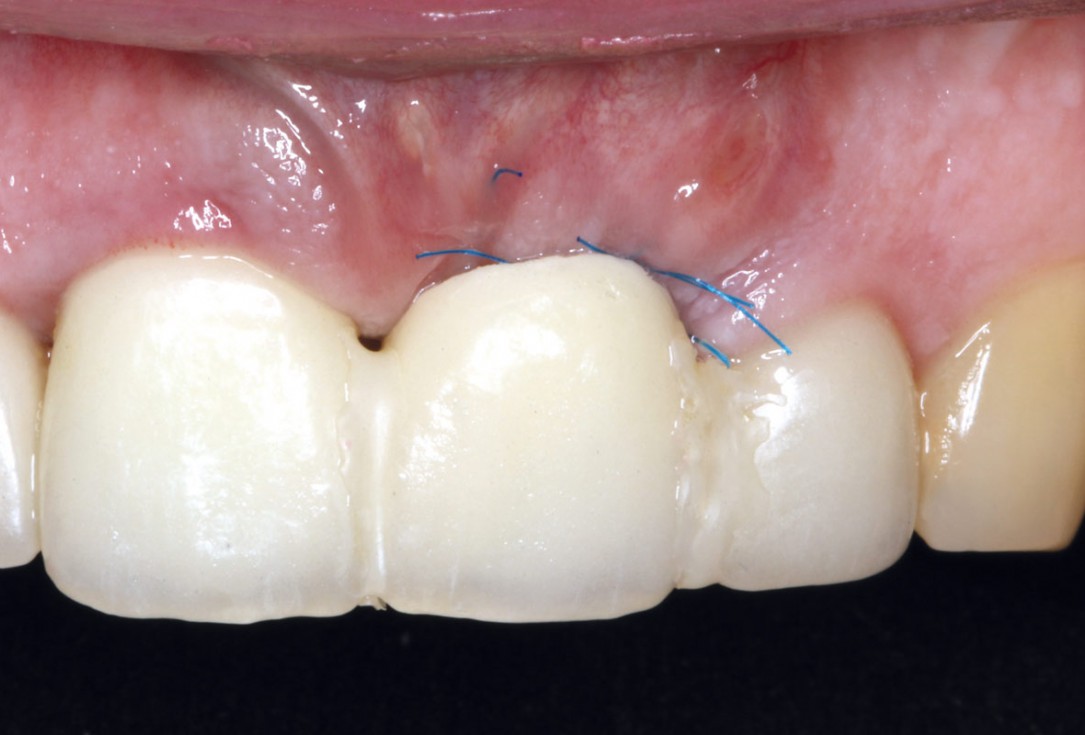

09/10 - Situation four months post-operative

Socket augmentation using mucoderm®, maxgraft® and Straumann® Emdogain® - Dr. A. Puišys